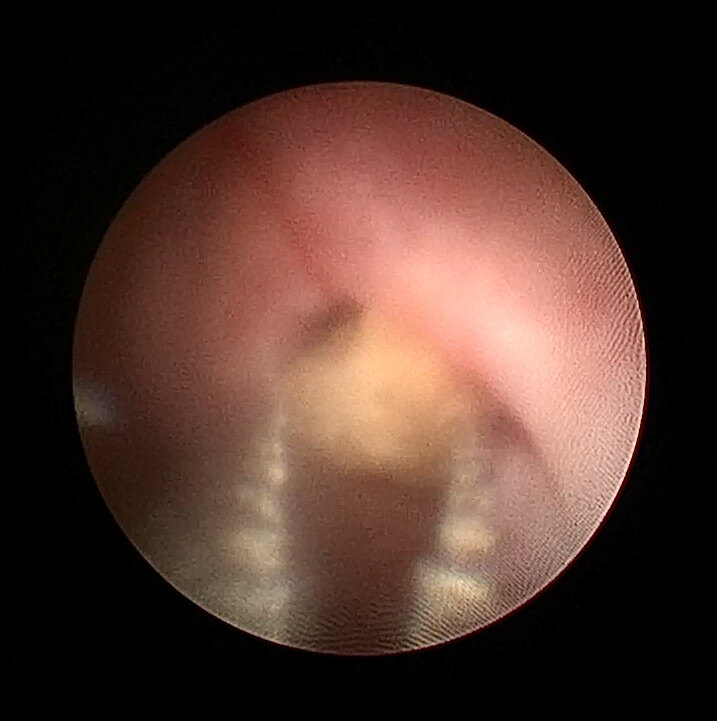

术中输尿管镜下发现右输尿管结石由于梗阻时间太长,已被息肉包裹,引起输尿管完全梗阻